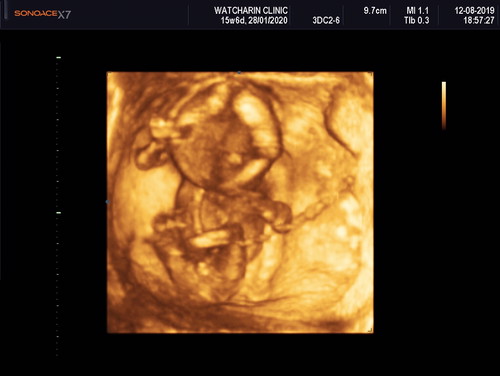

เพศลูก

ชายชัวร์ไช่ไหมค้ะซาวตอน4เดือน.? แอบผิดหวังอยากได้ลูกสาวมากๆ.?

เราเห็นมีจู๋น้ะ

นั่นน่าจะเป็นจุ๊ดจู๋น้องนะคะ บ้านนี้ก็อยากได้ลูกสาวเหมือนกันค่ะ แต่น้องก็มีจุ๊ดจู๋ 😂